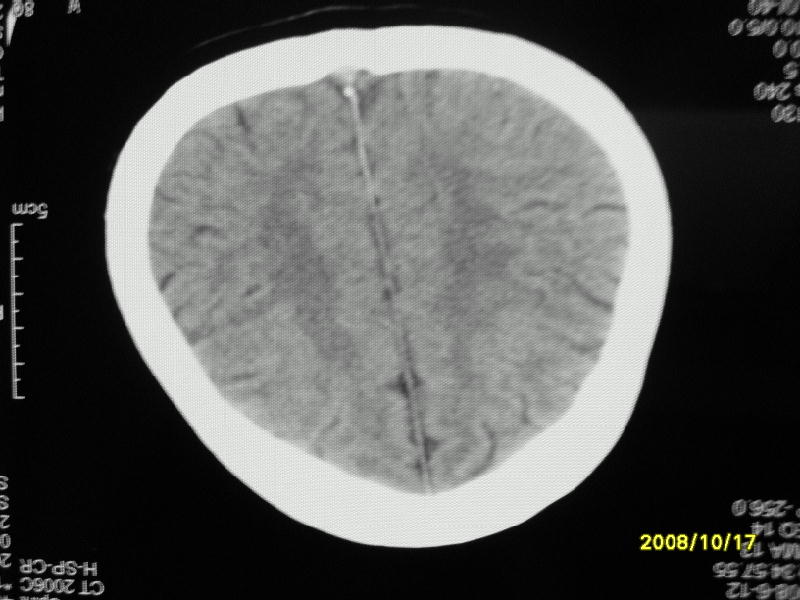

检查名称:     ct颅脑平扫           男     28岁

表现:左顶叶见斑点状致密影。边缘清,大小约0。3*1。0cm,余脑实质密度及灰白质结构示见异常。脑室系统大小,形态,密度未见异常。脑沟。脑裂。脑池未见异常密度影。中线结构无移位。

印象:左顶叶少许钙化灶

左顶叶见斑点状致密影。边缘清,大小约0。3*1。0cm,余脑实质密度及灰白质结构示见异常。脑室系统大小,形态,密度未见异常。脑沟。脑裂。脑池未见异常密度影。中线结构无移位。

印象:左顶叶少许钙化灶。

镰旁钙化

考虑脑膜钙化或脑膜血管钙化

支持 考虑脑膜钙化或脑膜血管钙化。

镰旁钙化或顶骨内板骨嵴部分容积效应,建议mri矢状位扫描观察与顶骨的关系。排外后者。

左顶叶见斑点状致密影